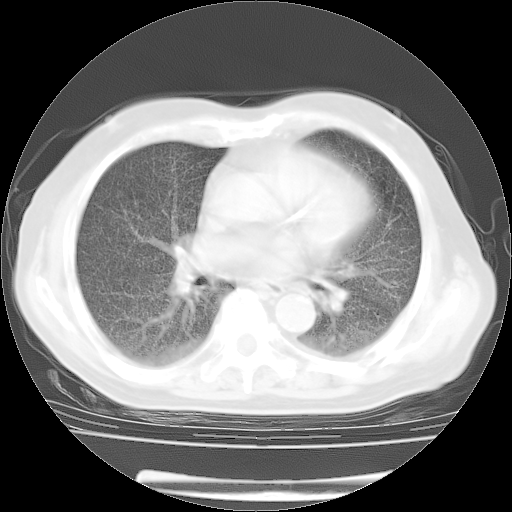

肺部CT平扫未见异常。